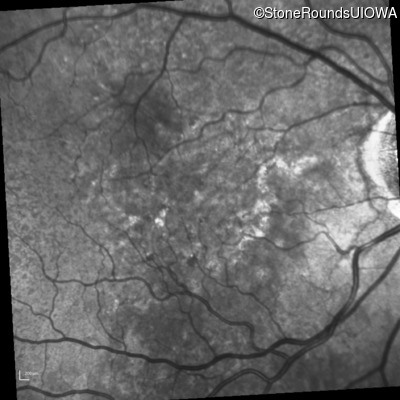

Infrared Fundus Photograph - Left - 20/30 -2 sc

Exemplar